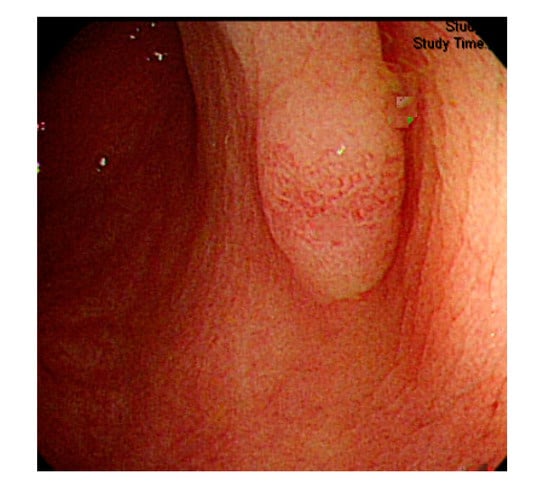

Figure 3.

Small texture of polyp and intestinal wall.